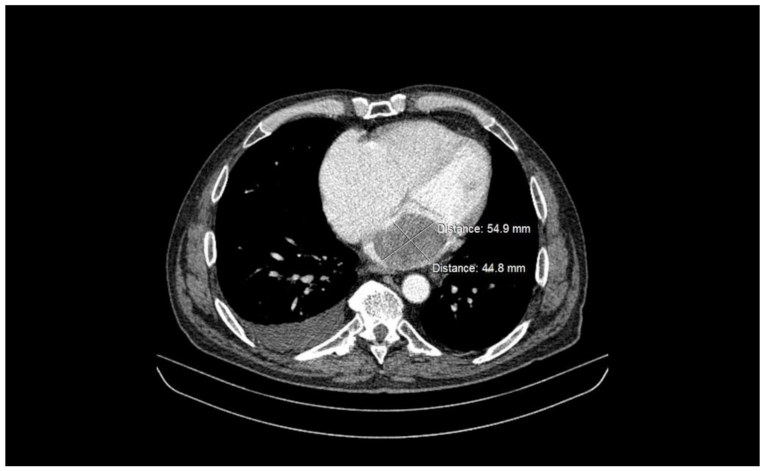

2.2. Preoperative Findings